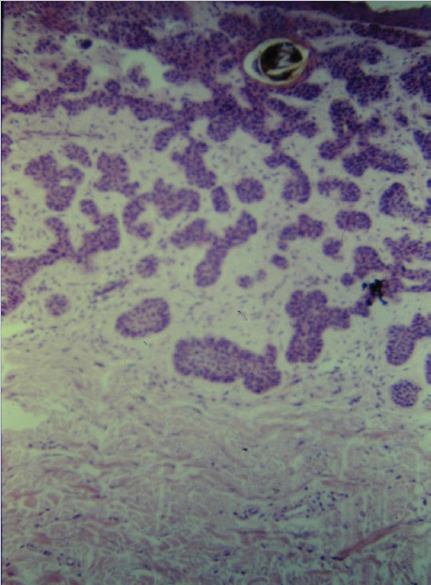

Fig. 3.16 Micronodular basal cell carcinoma (BCC) histopathology. Characteristic feature of small cell nests scattered through the tissue without surrounding stroma.